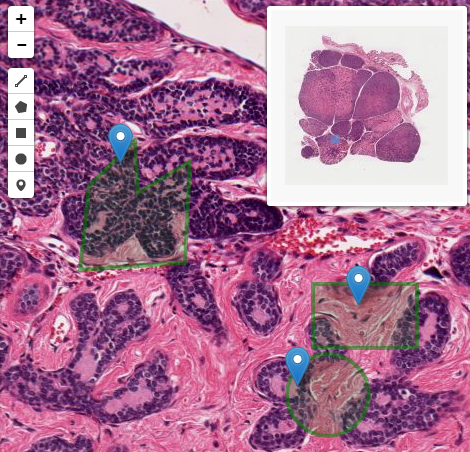

Cellular level resolution provides necessary information about the case. It is possible to precisely classify cells from overpopulated regions and predict type and stage of tumor

Every cell with it's surroundings contains a lot of relevant information. It can be used to simply classify tumor or healthy tissue. It can be also used to find unusual, atypical behavior to better understand the nature of the case

| Divide in Frames |

| ▼ |

| Frame segmentation |

| Extract frames of interest |

| Classify nuclei in a frame |

| Classify each frame |

| Classify the sample |